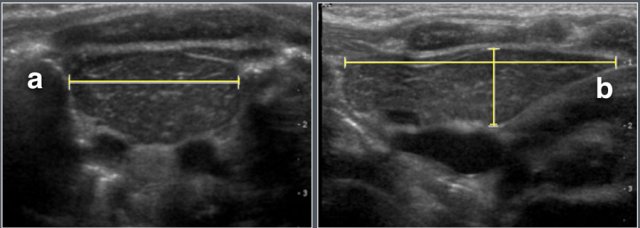

The maximum transverse diameter, right lobe anteroposterior, left lobe anteroposterior.

Perpendicular to the transverse plane the longest craniocaudal dimension (length) is assessed.

The thymic index was calculated by multiplying the transverse diameter (a) by the largest sagittal area (b).